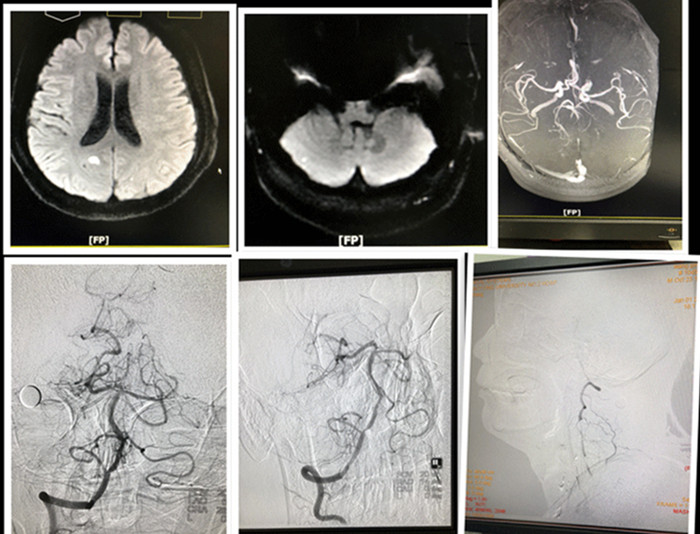

2018新年第一天中午12点,神经内科住院总高震医师接到急诊科电话,说有病人突发意识障碍、四肢活动不灵活,怀疑急性脑血管病,需急会诊,他立即奔赴现场。原来是一位54岁的男性,高血压多年,自己从没好好管过。根据患者病情,高震住院总医师及值班二线李燕玲主治医师初步诊断后循环急性脑梗死(基底动脉尖综合征?),病情危重,病程3个多小时,需要立即启动科室急诊溶栓绿色通道,他们给予静脉rt-PA溶栓;在静脉输注rt-PA同时,高震医师陪同患者急诊做了DWI及MRA,并将资料上传至科室溶栓取栓微信群,同时把病情电话报告给科主任张桂莲教授,在与家属简短交谈后,患者家属同意脑血管造影手术。这边介入专职护士蒋鹏鹏熟练地腹股沟区备皮——开造影包——碘佛醇试验,那边高震与一线值班医师任宏伟快速并有条不紊地消手——消毒——穿手术衣——穿刺——送管,这时张主任也匆忙从公公婆婆的生日宴赶到手术间。时间一分一秒的过去,张主任紧盯显示屏,仔细查看着造影的每根血管。听闻有急诊手术,张茹副主任医师在完成门诊后也赶到手术室,两位主任一起讨论着诊疗方案。经过1小时的全脑血管造影,发现患者多处脑血管病变,右侧椎动脉重度狭窄,左侧椎动脉起始段闭塞,应该是本次发病的责任血管,但经过及时静脉溶栓及造影手术,患者临床症状已完全恢复,暂时没必要冒险进行取栓术,随后血管是否需要再通,可根据后续病情决定。张主任详细向家属谈明了患者目前的情况及后续的诊治计划,与家属达成共识后结束了手术。当患者被护送回病房,抬病人、心电监护、调设静脉微量泵、穿刺伤口压迫、足背动脉观察......护士们熟练地干着所有的事情,至此,针对该患者情况,神经内科溶栓取栓团队的工作才算结束,而此时已进入新年第一天的傍晚,看见患者及家属喜悦的样子,医护人员们都会心地笑了。